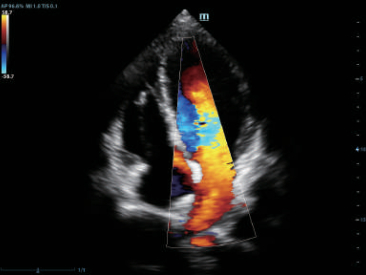

–Θ–Μ―¨―²―Ä–Α–Μ–Β–≥–Κ–Η–Ι –Η –≤―΄―¹–Ψ–Κ–Ψ–Ω–Μ–Ψ―²–Ϋ―΄–Ι –Ψ–±―ä–Β–Φ–Ϋ―΄–Ι –¥–Α―²―΅–Η–Κ –Ψ–±–Β―¹–Ω–Β―΅–Η–≤–Α–Β―² –Ω―Ä–Β–≤–Ψ―¹―Ö–Ψ–¥–Ϋ–Ψ–Β –Κ–Α―΅–Β―¹―²–≤–Ψ –≤–Η–Ζ―É–Α–Μ–Η–Ζ–Α―Ü–Η–Η –≤ –Α–Κ―É―à–Β―Ä―¹―²–≤–Β –≤ ―Ä–Β–Ε–Η–Φ–Α―Ö 2D, –Π–î–ö, 3D/4D –¥–Μ―è –±–Ψ–Μ―¨―à–Β–Ι –¥–Η–Α–≥–Ϋ–Ψ―¹―²–Η―΅–Β―¹–Κ–Ψ–Ι ―É–≤–Β―Ä–Β–Ϋ–Ϋ–Ψ―¹―²–Η –Η –Ω–Ψ–≤―΄―à–Β–Ϋ–Η―è –Κ–Α―΅–Β―¹―²–≤–Α –Η―¹―¹–Μ–Β–¥–Ψ–≤–Α–Ϋ–Η―è;